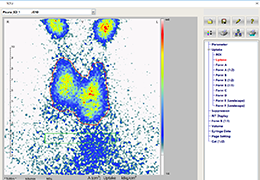

ANYTHINK 经导管主动脉瓣膜置换术分析系统